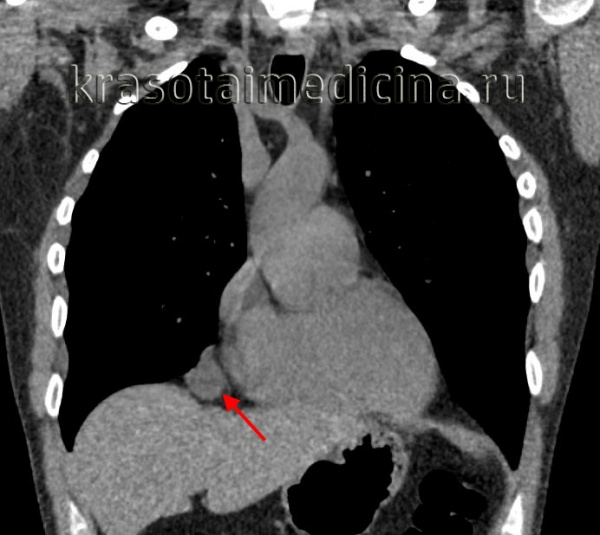

- Томографическая диагностика. Для более детальной оценки структуры, толщины стенок кисты, характера содержимого и взаимоотношения с соседними анатомическими образованиями, производится КТ и МРТ средостения.

- Эхография. При медиастинальных новообразованиях в диагностической практике широко используется УЗИ средостения. В диагностике кист перикарда существенно помогает ЭхоКГ, позволяющая дифференцировать кисту средостения от кист легкого, дермоидных кист средостения, аневризмы аорты.